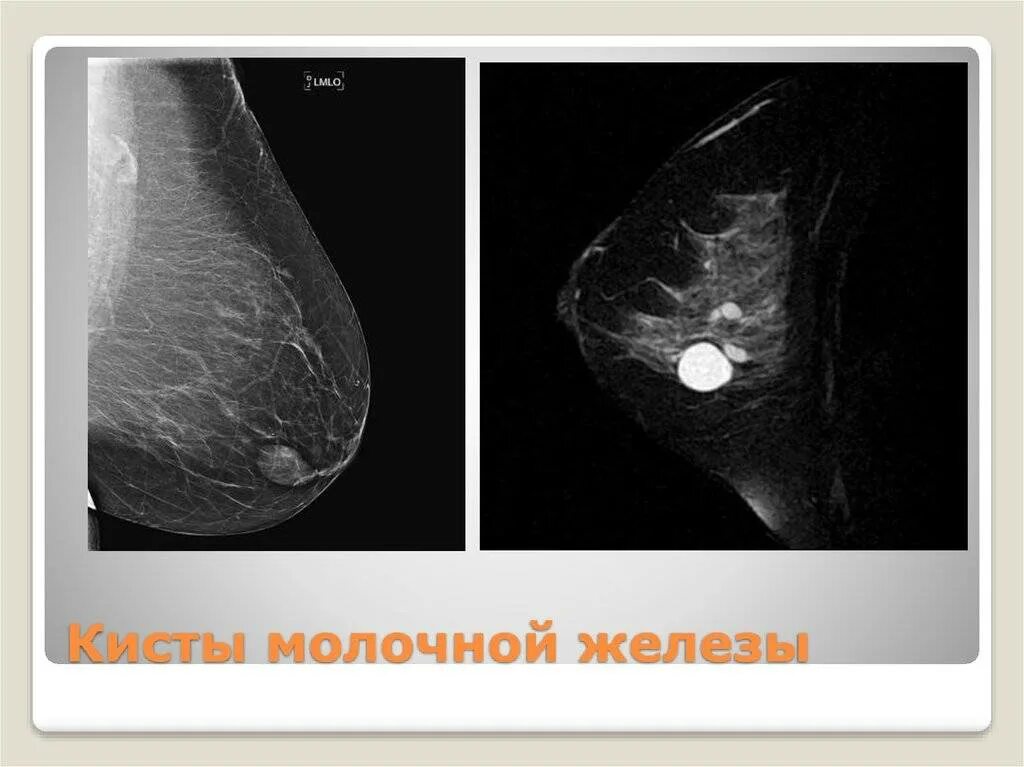

Как выглядит киста молочных желез